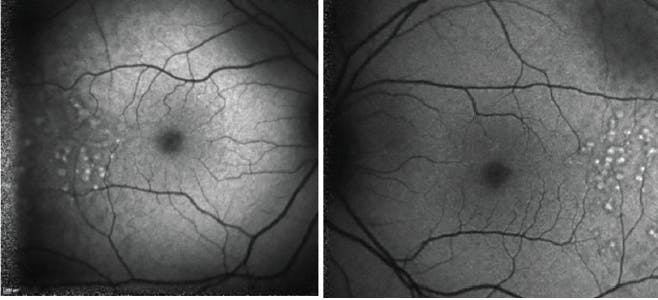

Color fundus photography images are presented in Figures 1 and 2. SD-OCT demonstrated large drusen in the temporal macula bilaterally, with no changes within the retina outside the foveal area (Figures 3 and 4).

<p>Figures 1 and 2. Color fundus photography images for left and right eyes at presentation.</p>

Figures 1 and 2. Color fundus photography images for left and right eyes at presentation.